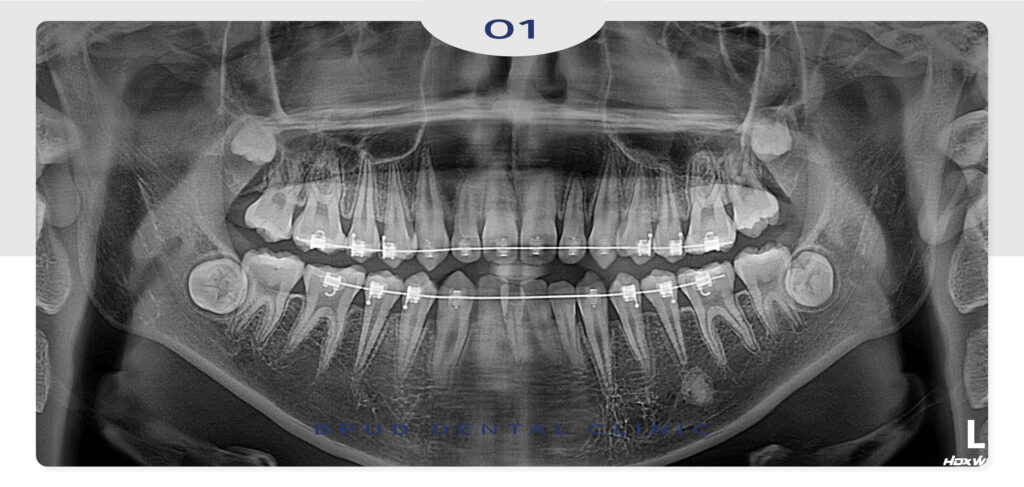

2024.03.23

2025.04.18

교정 중간 중간 충치치료도 함께

진행하셨는데요.